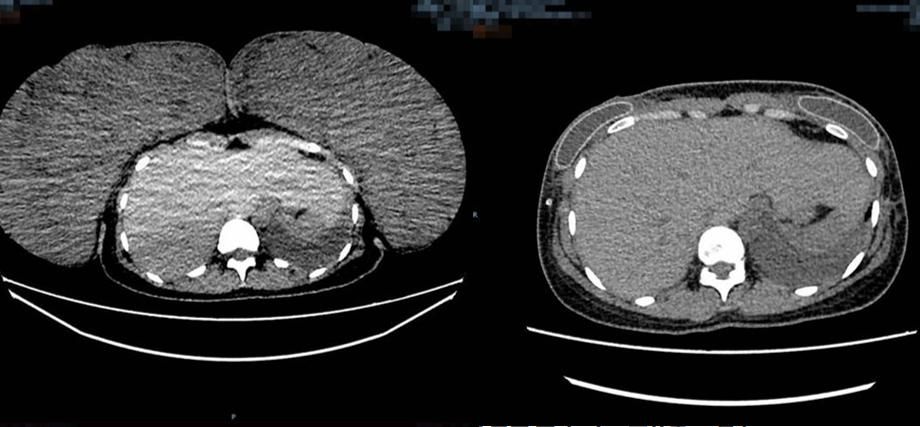

Comparison of the patient's chest enhancement CT. Preoperative size (left): 267 mm×100 mm×293 mm, postoperative size (right): 125 mm×270 mm×340 mm.

(Photo provided to Newsgd.com)